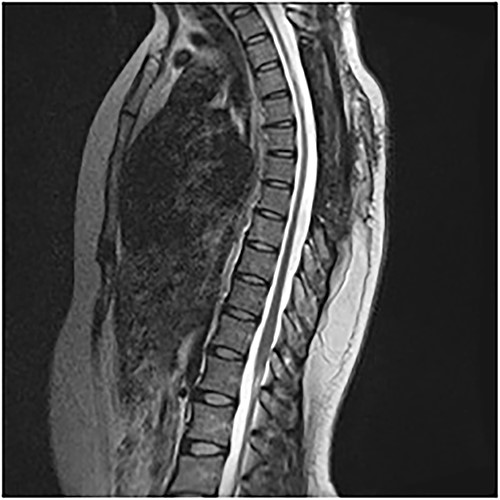

An MRI of the thoracolumbar spine was done, which showed an eccentrically located T4–7 cystic extradural mass causing severe cord compression. The spinal cord was flattened and displaced to the left (Figs 1 and 2).